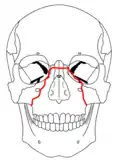

Le Fort I fractures

Le Fort II fractures

Le Fort III fractures

At the beginning of the 20th century, René Le Fort mapped typical locations for facial fractures; these are now known as Le Fort I, II, and III fractures (right).[7] Le Fort I fractures, also called Guérin or horizontal maxillary fractures,[14] involve the maxilla, separating it from the palate.[15] Le Fort II fractures, also called pyramidal fractures of the maxilla,[16] cross the nasal bones and the orbital rim.[15] Le Fort III fractures, also called craniofacial disjunction and transverse facial fractures,[17] cross the front of the maxilla and involve the lacrimal bone, the lamina papyracea, and the orbital floor, and often involve the ethmoid bone,[15] are the most serious.[18] Le Fort fractures, which account for 10–20% of facial fractures, are often associated with other serious injuries.[15] Le Fort made his classifications based on work with cadaver skulls, and the classification system has been criticized as imprecise and simplistic since most midface fractures involve a combination of Le Fort fractures.[15] Although most facial fractures do not follow the patterns described by Le Fort precisely, the system is still used to categorize injuries.[5]